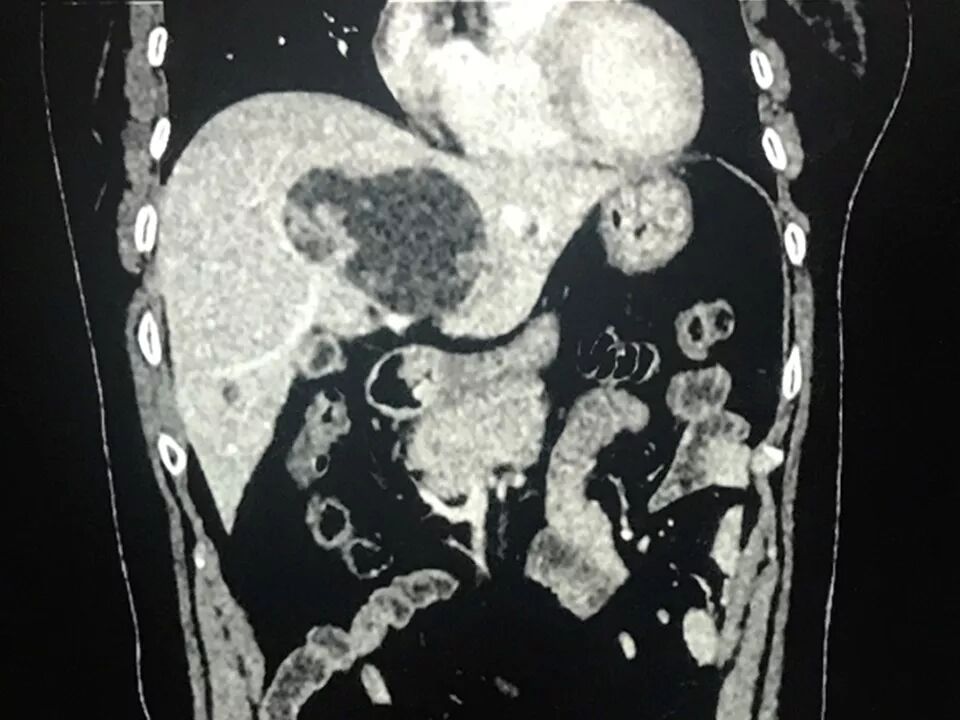

CT表现:

肝内单发占位灶,累及肝左右叶及尾叶。病灶平扫呈低密度,边缘见数枚等密度结节,无钙化,动脉期结节强化,呈等高密度;门脉期结节密度较正常肝实质呈相对稍低密度。